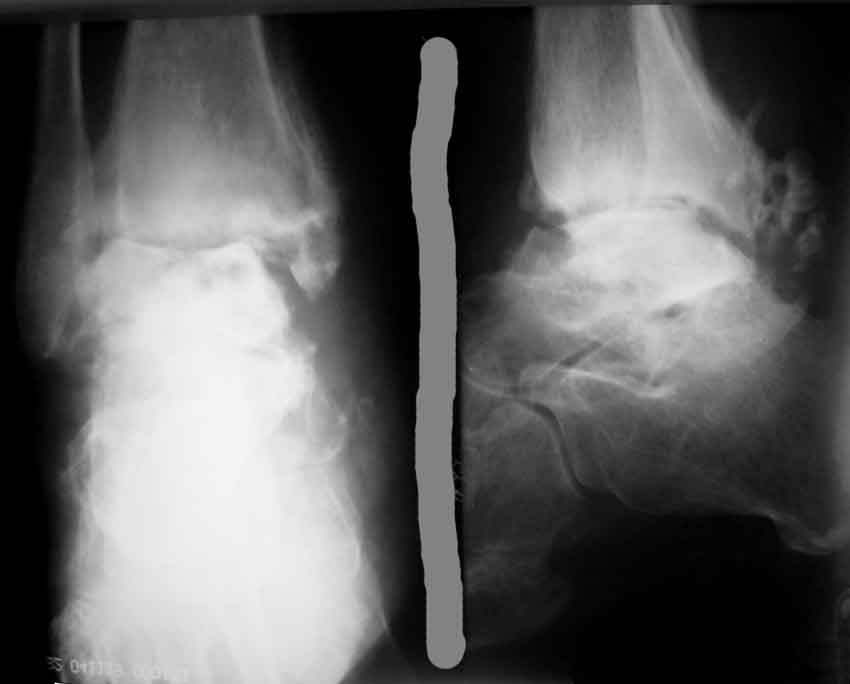

Хочется вынести на обсуждения ортофорума вопрос: - Как лечить асептический некроз таранной кости?

Пациент Е., 52 года,

Обратился в связи с болями при нагрузке в правом голеностопном суставе, ограничение движений.

Травма 26.06.2004 в результате падения с высоты(прыгнул с лестницы). Лечился стационарно с диагнозом закрытый перелом правой таранной кости, обеих лодыжек со смещением. Выполнено оперативное лечение - остеосинтез лодыжки спицами, гипс. В сентябре 2004 спицы удалены. В сентябре 2004 острый правосторонний илеофеморальный тромбоз. Проведен курс консервативной терапии. В мае 2005 года больному проводился курс стационарного консервативного лечения по поводу посттравматического артроз правого голеностопного сустава. В ноябре 2005 года повторное ухудшение состояния, усиление болей повторный курс консервативного лечения в диагноз добавлен посттромбофлебитический синдром. ХВН 3А ст правой нижней конечности. В приложении R- до удаления спиц и последние R-граммы.